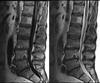

2 different views

Having said that, I haven't had the opportunity to examine you, and the large sequestered fragment at L5 doesn't look good. But at L3 and L4 you have distinct signs of stenosis too. What does the MRI report say about the body of L4?